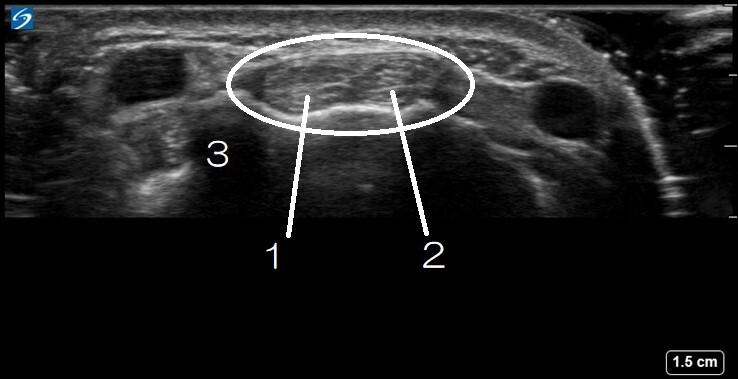

Wrist Compartment Two Image

1. Extensor Carpi Radialis Brevis

2. Extensor Carpi Radialis Longus

3. Lister’s Tubercle

Circled: Compartment 2